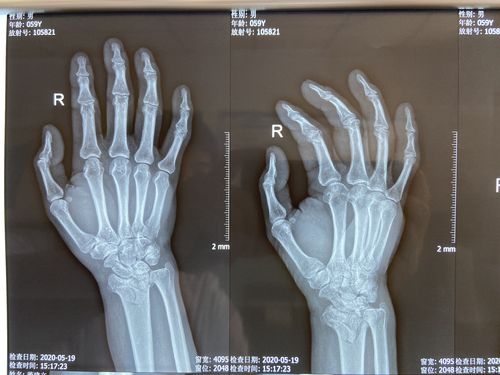

右侧桡骨远端骨折,舟骨骨折

11岁儿童桡骨远端骨折

右手桡骨远端骨折图片

桡骨远端骨折图片